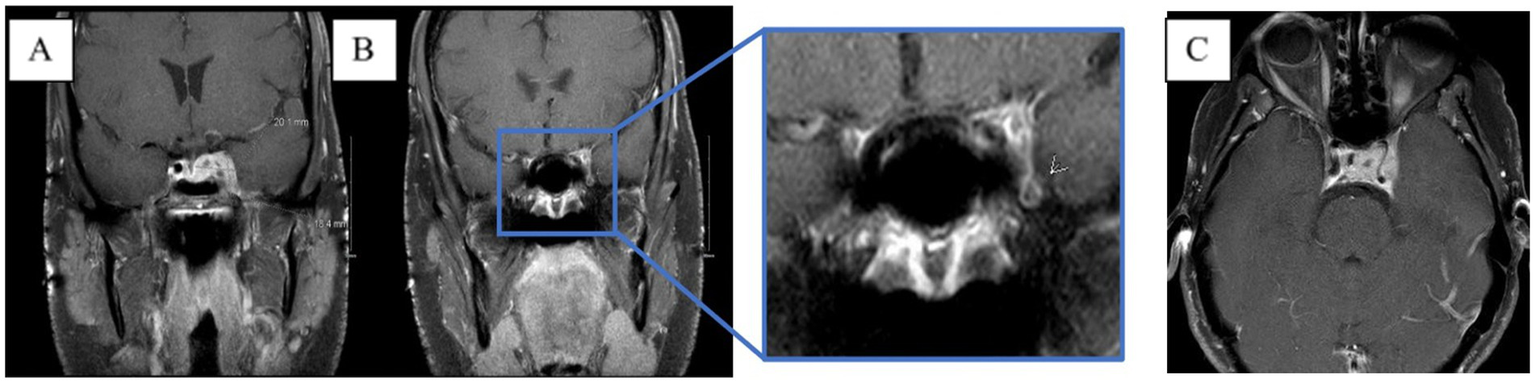

Figure 1

MRI skull base T1 + C at 6-week follow-up with reported improvement of symptoms. (A) Interval increase in the cavernous sinus mass size with extension into the pituitary fossa. (B) Subtle enhancement along V2 on the left, suggesting infiltrative process(inlet). (C) Narrowing of the left ICA.

Figure 3

MRI brain T1 + C when the patient lost corneal and pupillary reflexes. Subsequently transferred to the ICU. (A) Patchy enhancement within basal ganglia. (B) Worsened leptomeningeal enhancement around the suprasellar cistern. (C) Non-enhancing cystic focus suggesting thrombus or abscess.